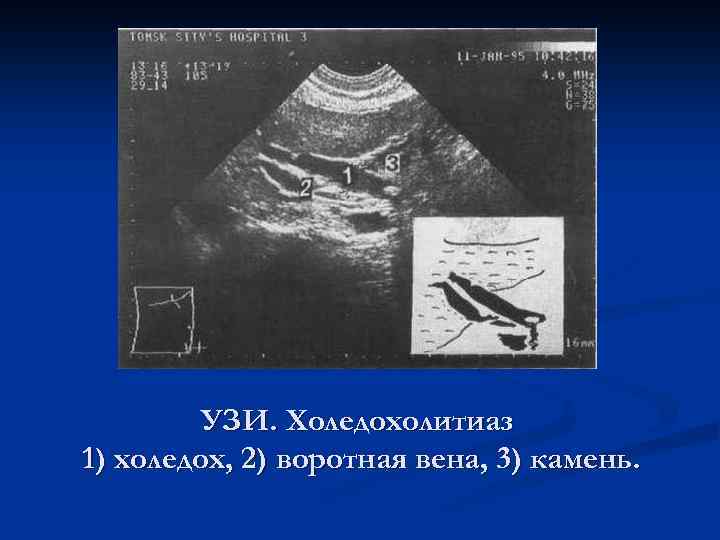

УЗИ. Холедохолитиаз 1) холедох, 2) воротная вена, 3) камень.

УЗИ. Холедохолитиаз 1) холедох, 2) воротная вена, 3) камень.